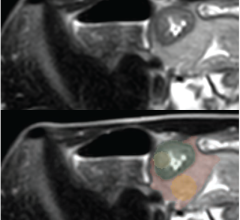

Nov. 10, 2025 — Researchers at Wayne State University and the Barbara Ann Karmanos Cancer Institute have developed a ...